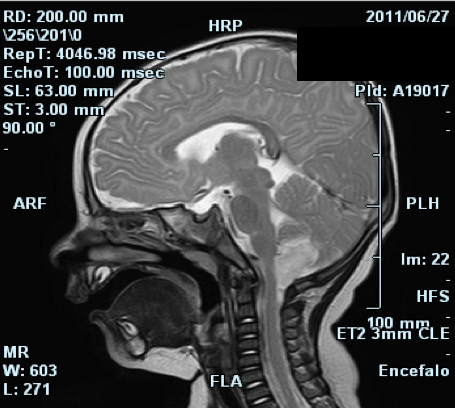

Il piccolo A. di 7 mesi, � giunto in PS verso le 21.30 di sabato sera, appena dopo essere sbarcato con la famiglia dal traghetto che doveva portarli in vacanza. Durante la traversata in occasione di un cambio pannolino A. � caduto dal letto a castello, sbattendo la fronte. Per questo i genitori preoccupati lo portano nel nostro ambulatorio di accettazione pediatrica. All'E.O.G. il piccolo � apparso in discrete condizioni generali, vigile, reattivo; pupille isocoriche, isocicliche e normoreagenti alla fotostimolazione; obiettivit� cardiopolmonare nella norma, FC 100 bpm, PA 90/60 mmHg, Sat.O2 100% in aria ambiente; addome trattabile, apparentemente n� dolente n� dolorabile; lieve escoriazione in regione frontale sx. Sottoposto a visita neurochirurgica (nella norma), � stata predisposta l'osservazione presso la Clinica Pediatrica. All'ingresso in reparto, ha eseguito esami ematochimici di routine e profilo coagulativo risultati nella norma. Verso le 22.30 in seguito alla comparsa di due episodi di vomito il piccolo ha iniziato terapia reidratante con souzione bilanciata alla velocit� di 30 ml/h. Dopo una notte tranquilla, per il riscontro di sonnolenza ed un ulteriore episodio di vomito � stata richiesta TAC-cranio urgente che ha escluso lesioni post-traumatiche, evidenziando per� un'area ipodensa in fossa cranica posteriore, a livello della tonsilla di dx, di dubbia interpretazione. Per tale motivo il giorno seguente, il paziente ha eseguito RMN-encefalo con MDC e Angio-RMN encefalo. Il primo esame ha confermato in sede cerebellare inferiore dx la presenza di una lesione espansiva di circa 1,5 x 1,5 x 2,5 cm, disomogeneamente iperintensa in T2, isoiperintensa in Flair, ipointensa in T1 con restrizione della diffusione ed esili strie di enhancement dopo la somministrazione di MDC. (Figura 1 e Figura 2)

Nel suo contesto si apprezzano minute aree ipointense in T2 da riferire a esiti di micro sanguinamenti. La lesione anteriormente contrae rapporto con l'arteria cerebellare postero inferiore, esercitando una lieve impronta sulla superficie posterolaterale dx del bulbo e infiltrando la tonsilla cerebellare omolaterale che appare modicamente ptosica al di sotto del forame occipitale (5 mm); superomedialmente esercita una modica impronta sul verme. Un'alterazione di segnale che potrebbe rappresentare segno d'infiltrazione controlaterale si apprezza a livello della tonsilla cerebellare di sx. Lateralmente la lesione appare delimitata da una stria di alterato segnale compatibile con edema perilesionale. Le restanti strutture cerebrali risultano nella norma. Lo studio angioRMN non evidenzia presenza di definite alterazioni a carico dei principali vasi arteriosi intracranici. Per le caratteristiche evidenziate, la giovane et� e la sede, il radiologo pone in prima ipotesi il sospetto di medulloblastoma, non potendo escludere per� una forma desmoplastica o un ependimoma. Non si rilevano ulteriori alterazioni di segnale a carico delle regioni sotto e sopratentoriali. Data la lontananza dal domicilio, i genitori del piccolo, in accordo coi sanitari, decidono di trasferire A. presso l'Unit� di Neurochirurgia della loro citt�. All'arrivo in Ospedale il piccolo appare sveglio, reattivo, con pupille isocoriche, normoreagenti. Muove i 4 arti senza apparenti asimmetrie, n� clonie. Presenta buon tono di arti, tronco e capo. Il piccolo A. � sottoposto ad intervento chirurgico per asportazione della lesione. Dall'esame istologico si evidenzia che il materiale accoglie lembi di parenchima cerebellare con associate numerose strutture vascolari proliferanti (saltuarie figure mitotiche) per lo pi� a parete sottile sullo sfondo di aree di microinfarcimento emorragico, numerosi elementi istiocitari e fenomeni di densa gliosi perilesionale. Particolarmente in due frammenti si repertano inoltre espressioni di necrosi e di flogosi suppurativa. I reperti suggeriscono una natura primitivamente vascolare della lesione di tipo angiomatoso.

Figura 1. RM dell'encefalo